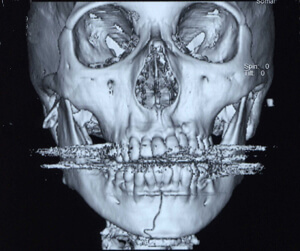

③顎骨骨折

顎骨骨折では軟組織損傷を伴うことが多く、出血、疼痛、腫脹などを認めることから救急処置が優先されます。

顎骨骨折の治療では単純に骨片線を整復するだけでなく咬合や咀嚼機能の回復が重要です。治療法としては非観血的治療と観血的治療(入院下手術、プレートなどによる固定)に大別されます。骨折した骨にずれがない場合、ワイヤーによる結紮固定や牽引などの非観血的治療を行う事があります。骨折した骨にずれがあり、咬合に異常を認める場合、金属プレート・スクリューを使用して骨折部の整復固定し、咬合の回復を図ります。